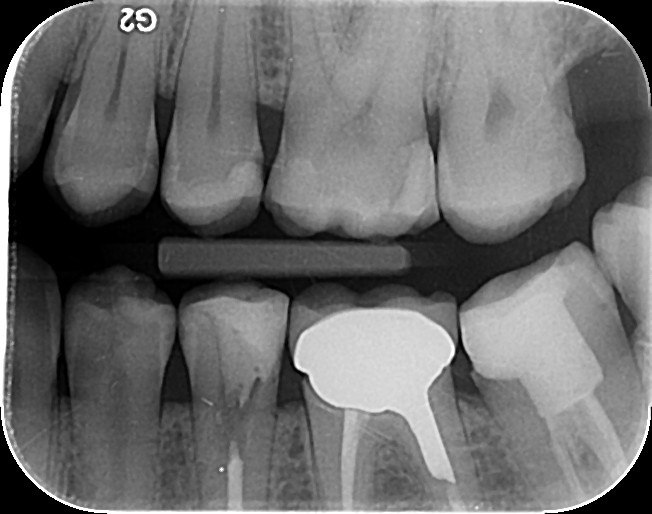

1. Which surfaces shows dental caries?

2. Which surface needs restoration?